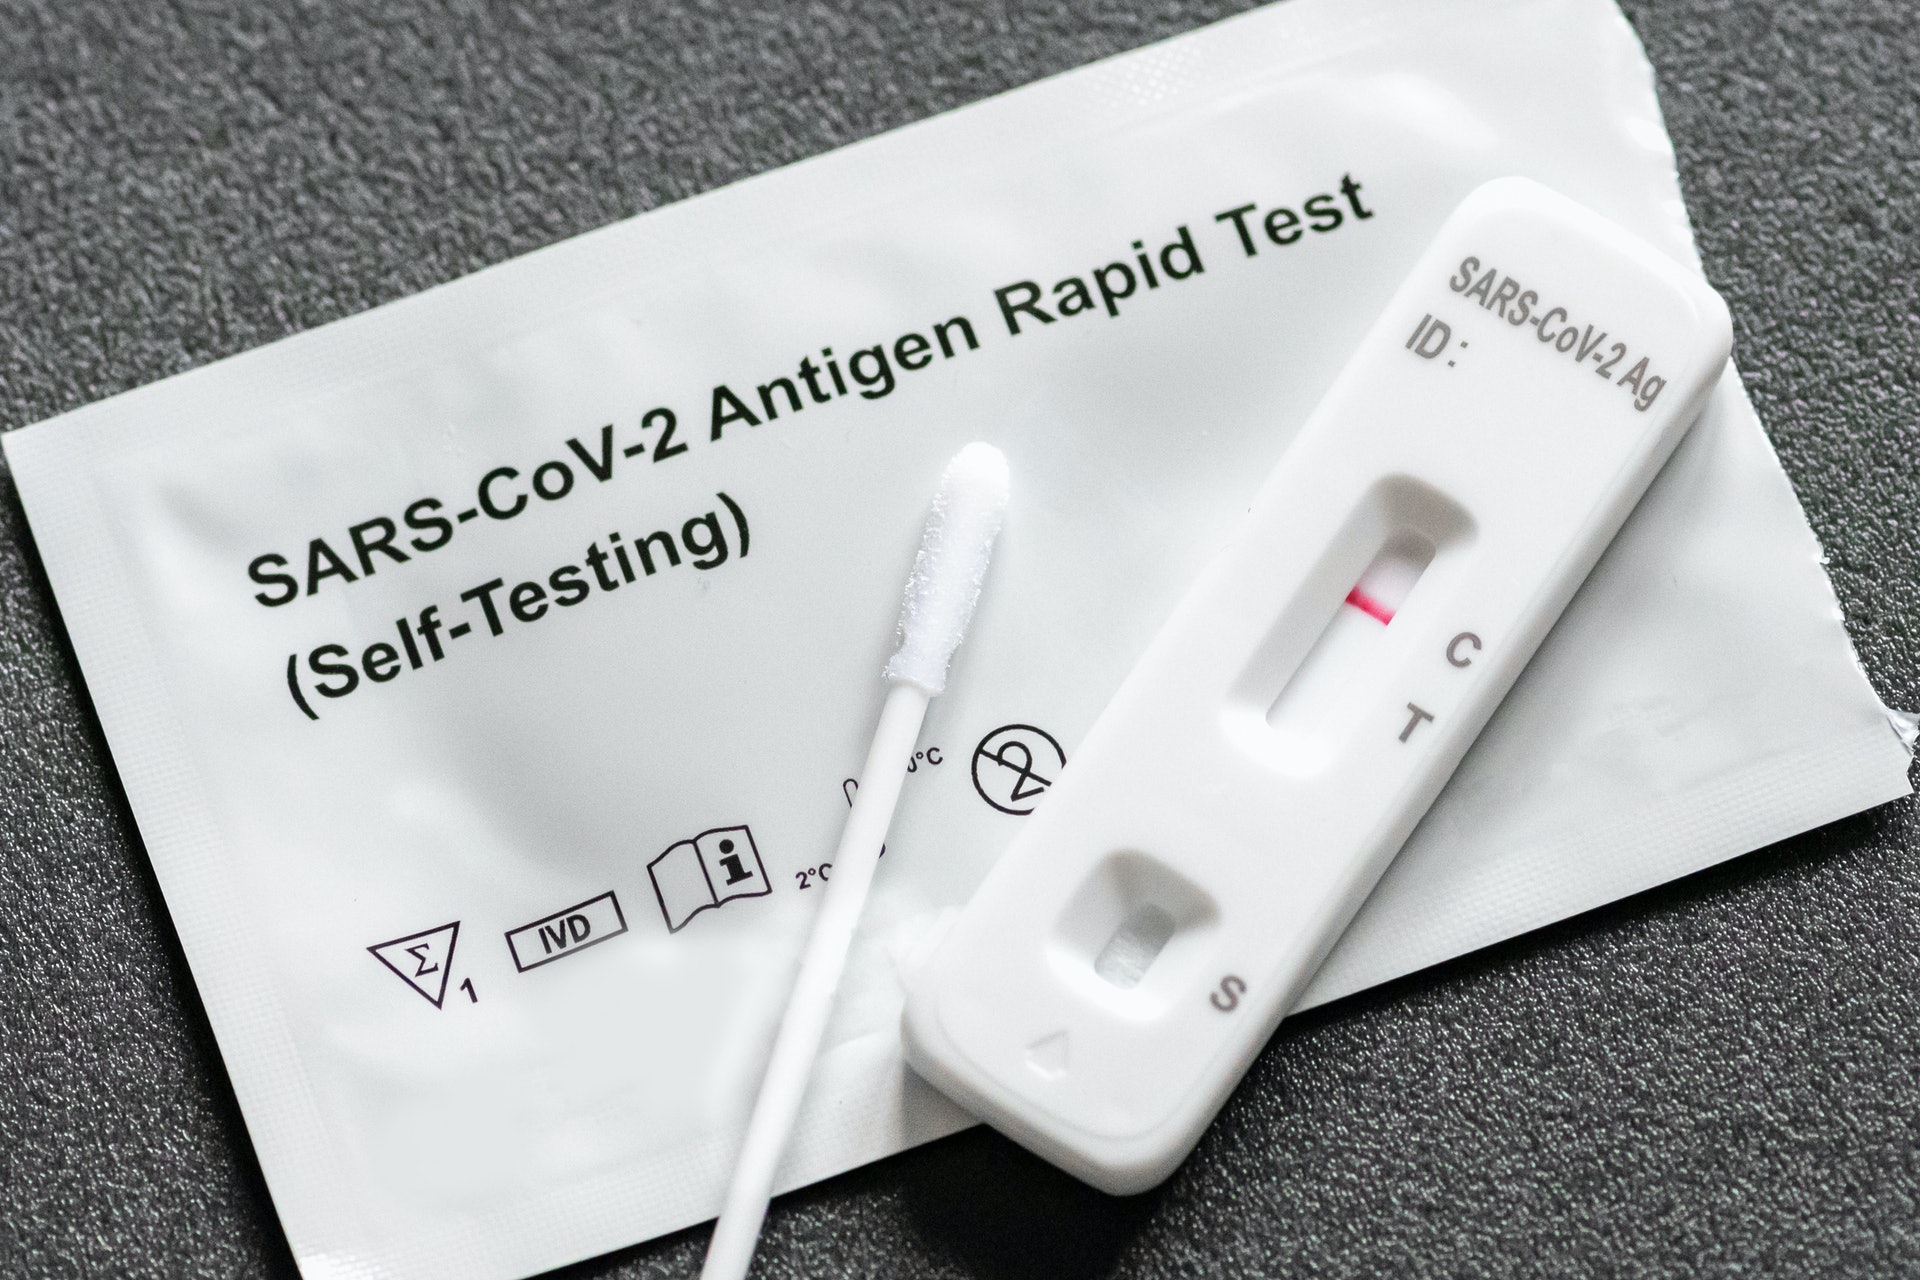

1 i. F0 `2 y9 wwww2.tvboxnow.com醫生更補充道,若打齊疫苗感染重症比率都不算高,如有病徵的話,自己於家中使用自我檢測便可以,核酸檢查「大可不必」,因大家最主要都只是想知道自己感染後是否有傳染性,而自我測試比核酸更好,只要有線即代表有傳染性,沒有線即沒有。而核酸檢測的測試太過準確,即使病毒量很低,沒有傳染性都仍會顯示陽性,若根據核酸來決定能不能上學上班得話,「社會很難正常運作」。 |